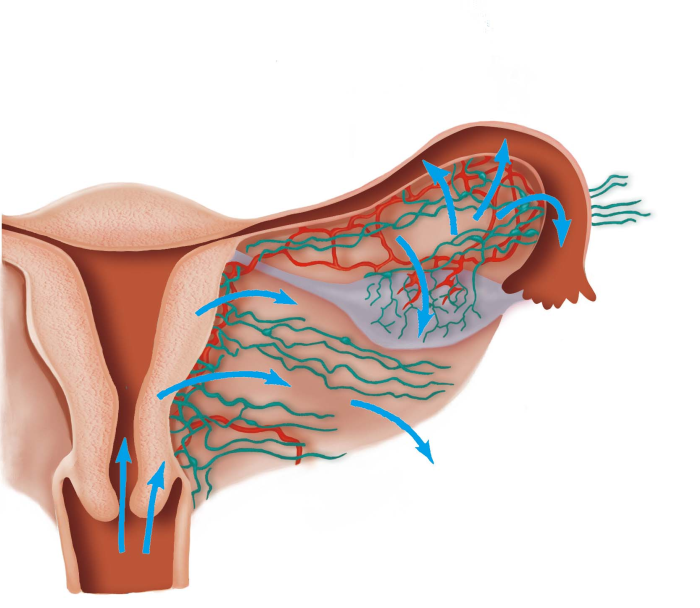

2.经淋巴系统蔓延 病原体经外阴、阴道、宫颈及宫体创伤处的淋巴管侵入盆腔结缔组织及内生殖器其他部分,是产褥感染、流产后感染及放置宫内节育器后感染的主要感染途径。链球菌、大肠埃希菌、厌氧菌多沿此途径蔓延。(图20-2)

图20-2 炎症经淋巴系统蔓延